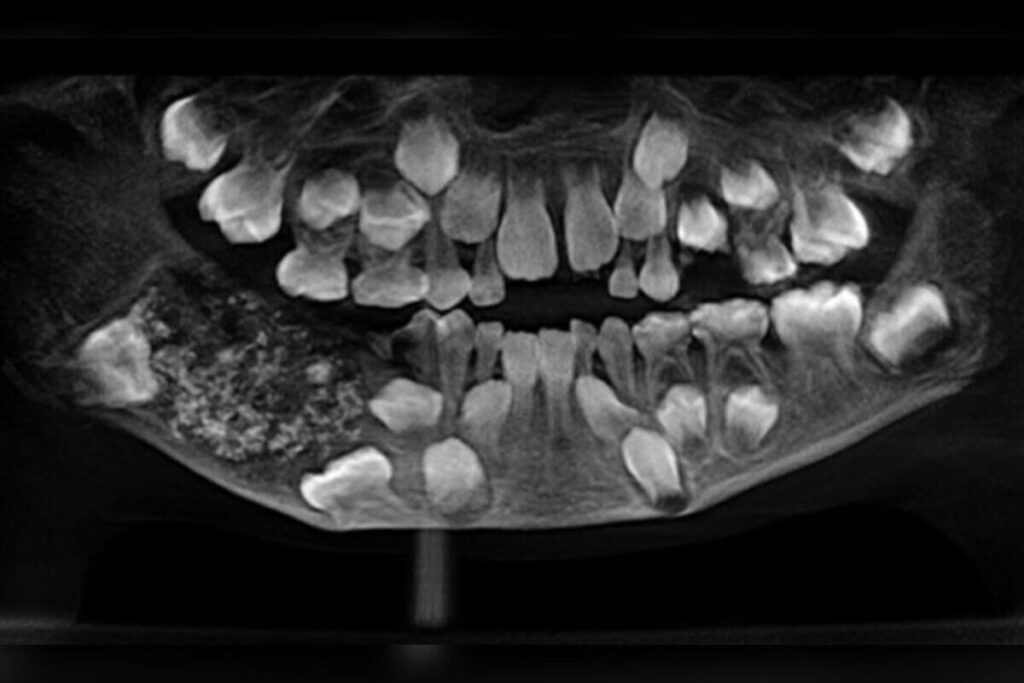

Durante uma cirurgia realizada em 2019, no Saveetha Dental College and Hospital, médicos encontraram 526 dentes em miniatura dentro de uma massa localizada na mandíbula do garoto.